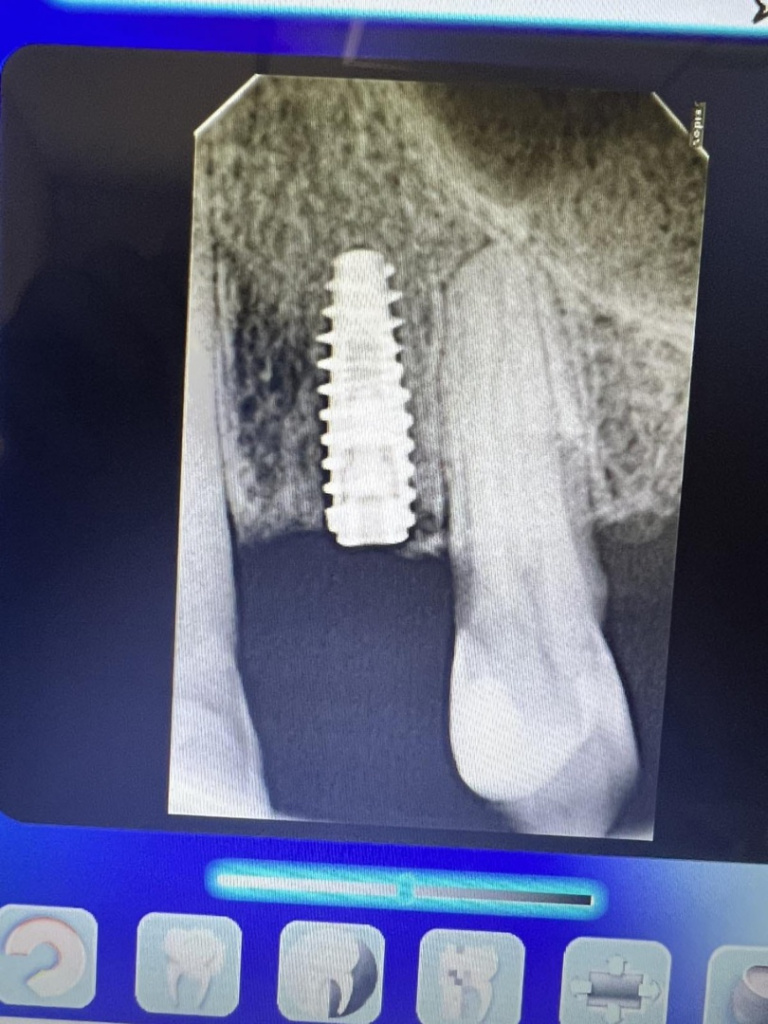

Доктор,первый раз установил имплант UI 3,6*10 классическим протоколом под заглушку с первичной стабильностью 30N.